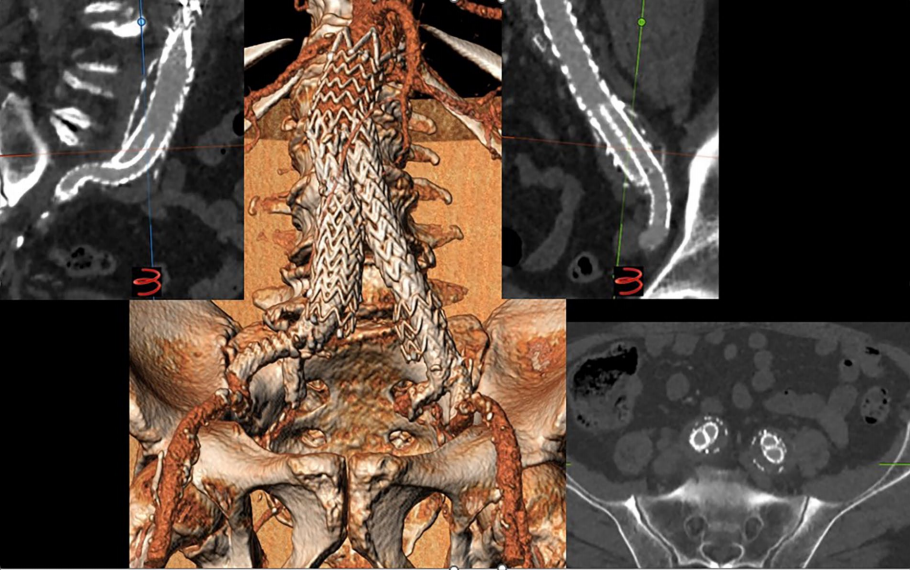

CERIB技术的另一个适应症是用于治疗先前EVAR失败的患者。最近有报道称,在开放手术或EVAR后进行使用IBD的腔内治疗在长达3年的时间内是安全有效的。然而,使用IBD有特定的严格解剖学标准,在本研究中,CERIB技术似乎是一个更简单的选择,取得了良好的结果且没有任何解剖限制(图3)。此外,先前使用的IBD并不干扰CERIB技术的应用。采用CERIB技术,也可以根据每位医生的经验或患者主髂动脉解剖结构,使用自膨或球扩覆膜支架。

图3 CTA示先前EVAR失败并随后接受CERIB技术的患者,其球扩覆膜支架通畅性良好。